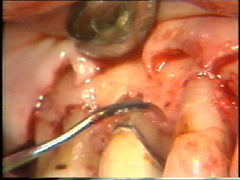

Se realiza una segunda  insición horizontal en el fondo de la bolsa  para facilitar el levantamiento del tejido de granulación

El levantamiento del tejido de  granulación se realiza en un tiempo y el procedimiento en sí es exigente. Puede hacerse antes o después del levantamiento del colgajo. El sangrado  se controla bien y el tiempo de exposición del hueso al medio bucal es reducido, cuando el tejido de granulación es eliminado antes del levantamiento del colgajo.